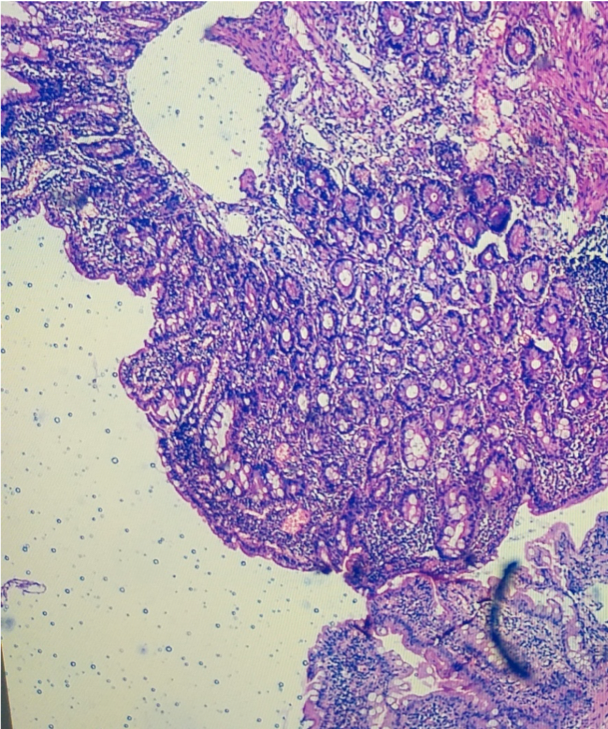

Repeat USG done at YMC-normal Bone marrow was done as had bicytopenia – to rule out the involvement of marrow by the disease process. Previously done duodenal biopsy slide was brought and subjected to 2nd opinion.Fig2

Loose stools reduced. Patients duodenal biopsy review done and tropical sprue considered in view of the crypt hyperplasia, abscess hence anti-TTG was negative.

The patient was finally diagnosed as Tropical sprue and started on Doxycycline and iron, vitamin supplements. patients diarrhea resolved, appetite improved and at follow up anemia improved and weight gain present

Though the patient was diagnosed as biopsy-proven celiac disease his condition was worsening even with a gluten-free diet and weight loss progressed which made us consider an alternative diagnosis. Considering close differentials to celiac sprue was tropical sprue as he was residing in the tropical area. Subjecting his old biopsy after discussing clinical background with pathology and sending serum antibodies showed features more favoring tropical sprue and patient symptoms significantly improved with prolonged antibiotic and nutritional supplements.